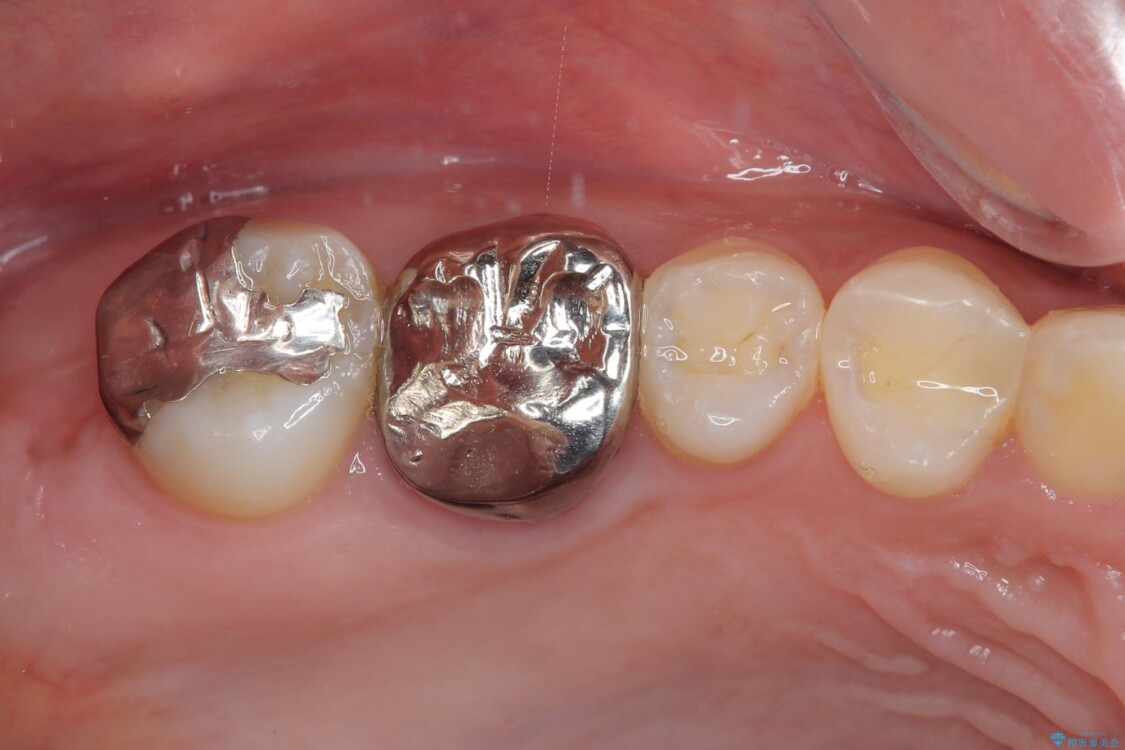

しかし、噛み合わせの相手である右上の第二大臼歯が、長期間噛み合う歯がなかった影響で**挺出(歯が下に伸びてくる状態)してしまっており、このままではインプラントを埋入して被せもの(上部構造)を入れるためのスペースが不足している状態でした。

その後、挺出していた右上第一大臼歯と第二大臼歯に装着されていた銀歯についても、審美性と適合性の向上を目的に、オールセラミッククラウンにやり替えました。

治療途中

• 挺出歯を圧下してスペースを確保!目立たない部分矯正で下顎大臼歯にインプラント治療を実現 治療途中画像